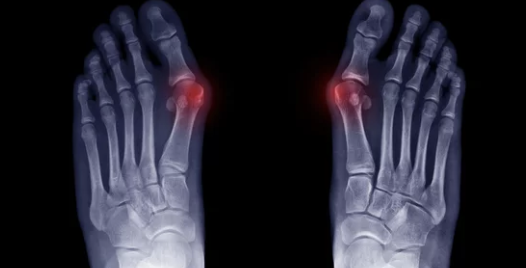

무μ§μΈλ°μ¦μ μμ§λ°κ°λ½μ΄ λ λ²μ§Έ λ°κ°λ½ μͺ½μΌλ‘ νμ΄μ§κ³ , μμ§λ°κ°λ½ κ΄μ μμͺ½μ΄ νμ΄λμ€λ μ§νμ λλ€.

무μ§μΈλ°μ¦μ λ°©μΉνλ©΄ ν΅μ¦μ΄ μ¬ν΄μ§κ³ λ° λ³νμ΄ λμ± μ¬ν΄μ§ μ μμ΅λλ€.

- λ§μ± ν΅μ¦: μμ§λ°κ°λ½ κ΄μ λΆμμ ν΅μ¦μ΄ μ§μλκ³ , λ€λ₯Έ λ°κ°λ½μλ ν΅μ¦μ΄ λ°μν μ μμ΅λλ€.

- λ° λ³ν μ ν: μμ§λ°κ°λ½μ΄ λμ± νμ΄μ§κ³ , λ€λ₯Έ λ°κ°λ½λ λ³νλ μ μμ΅λλ€.